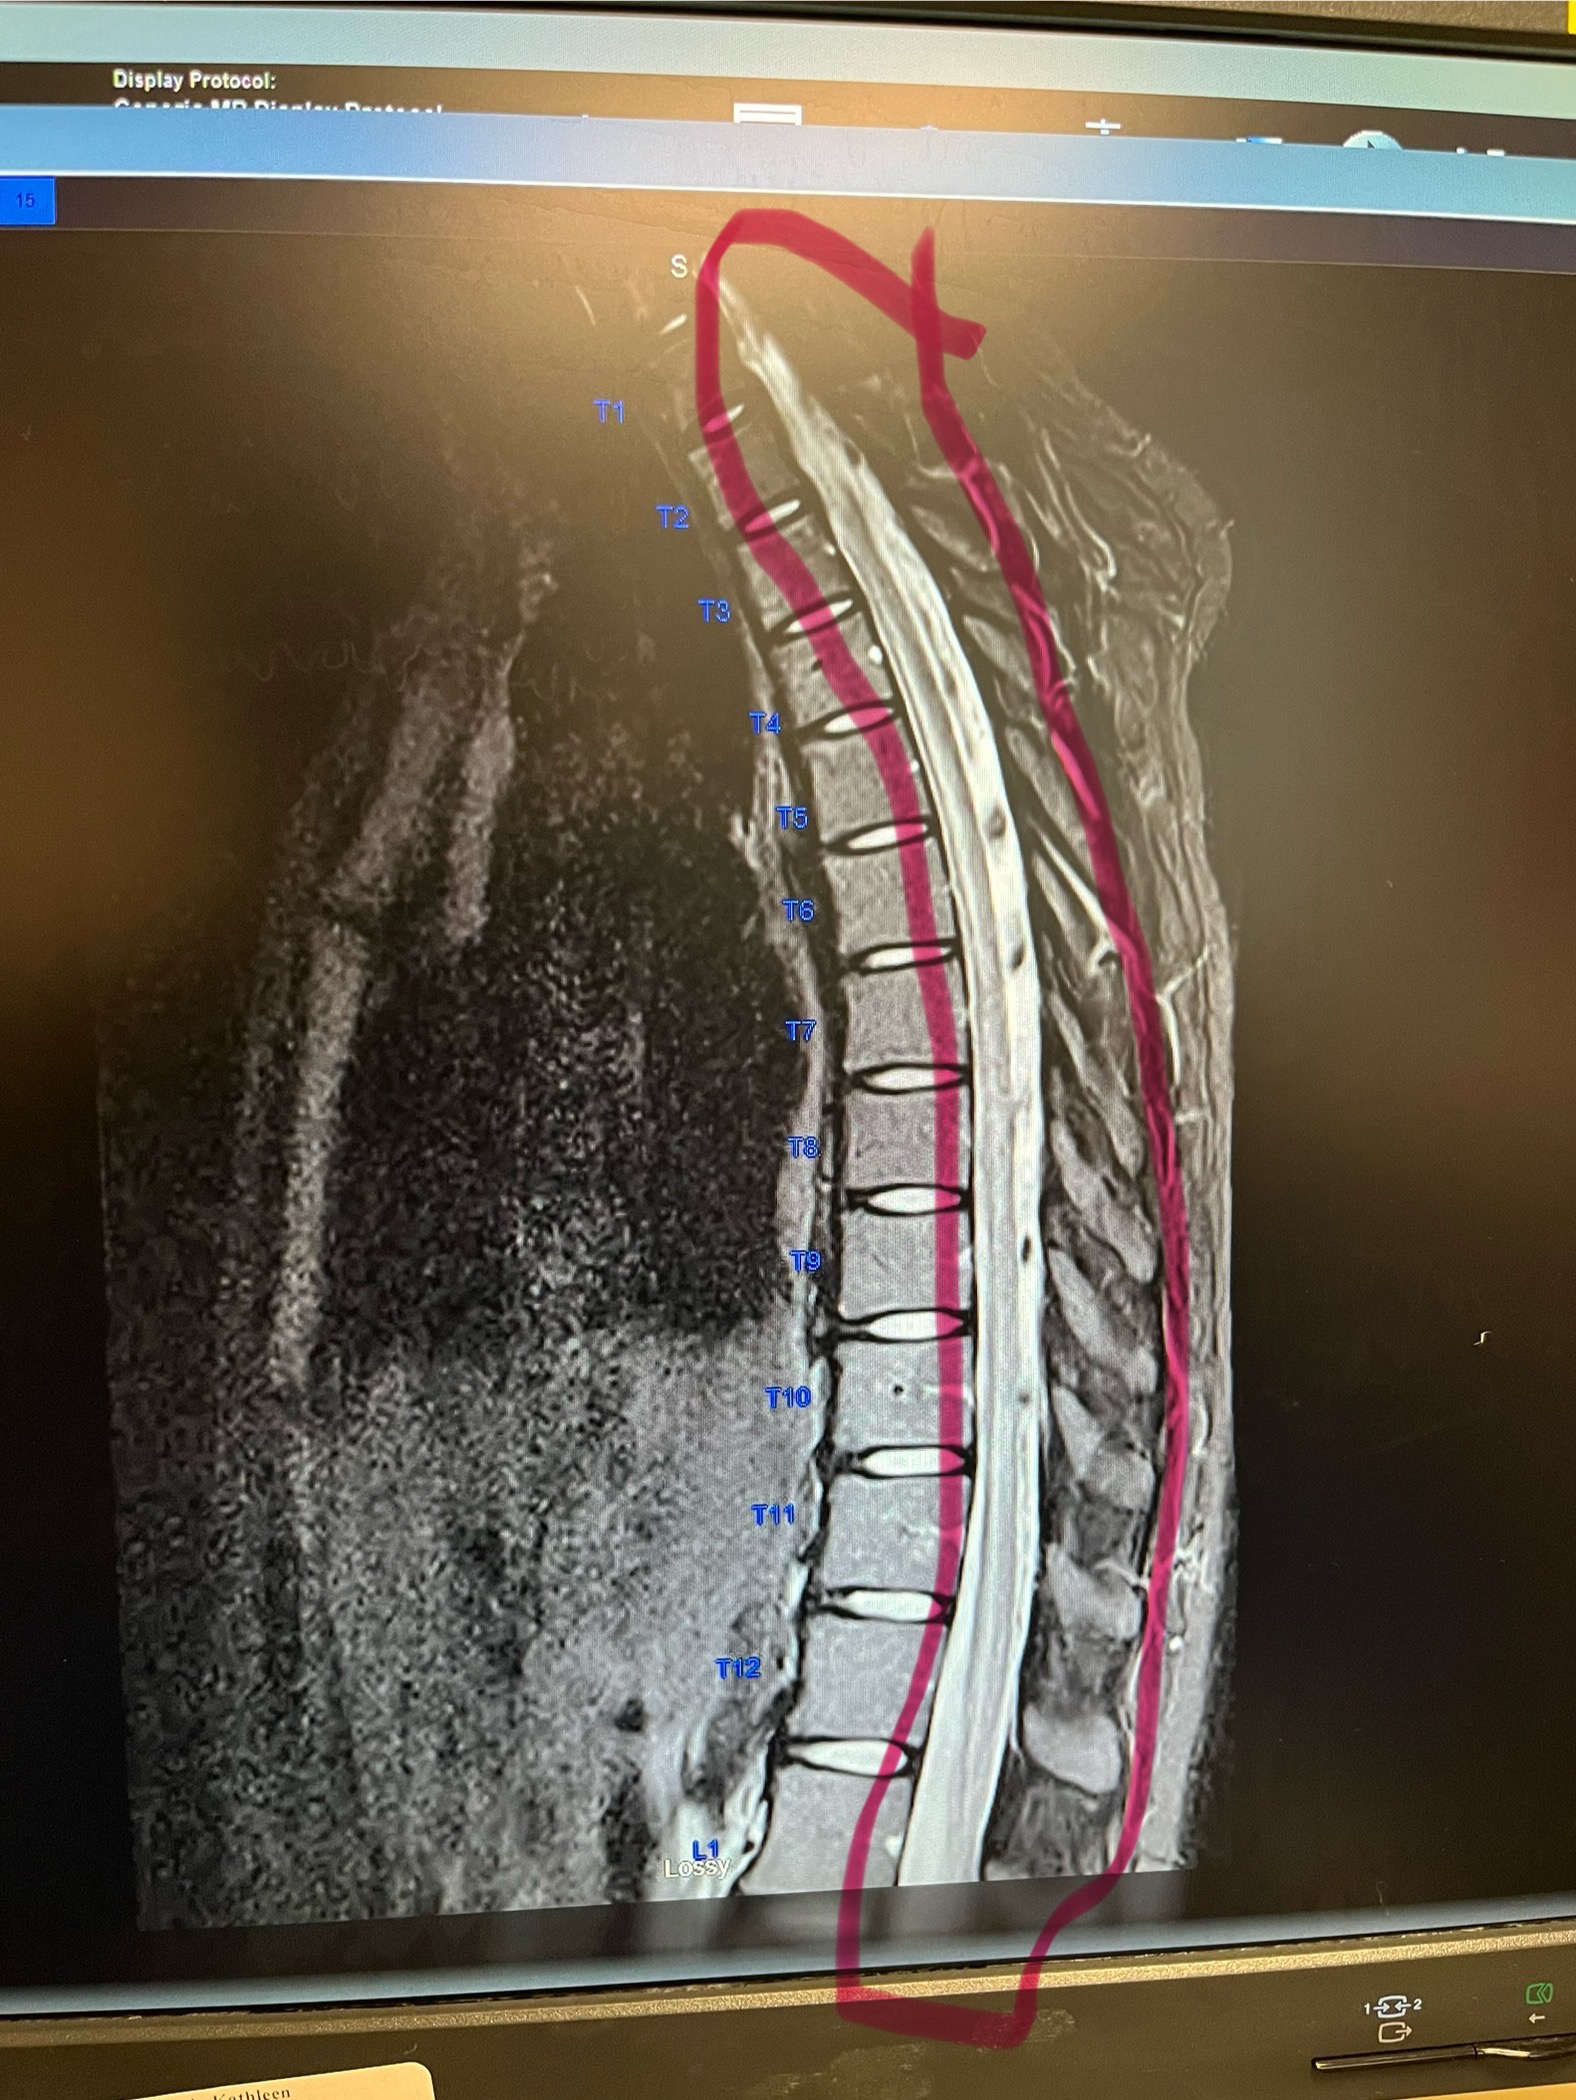

As many of you know, my best friend was diagnosed with acute transverse myelitis from West Nile virus. Less than 1% of people who contract west Nile develop this so there is not much research on it. Kayla lost the ability to walk and see on October 10, 2025. She was admitted to the hospital where they did every test they could think of. The MRI showed inflammation inside her spine, which was causing her so much pain and also causing her to lose the ability to walk. They said it was the worst they have ever seen. The CT scan also showed blood clots in both of her lungs. She was extremely lucky that they were small enough when they passed her heart that she did not lose her life. Her heart is working hard fighting this virus, making it hard to do physical therapy. Her heart rate jumps up to 200 while trying to walk with physical therapy. She will soon be transferring over to a rehab facility where she will be for several weeks, working on gaining muscle strength back. They do not know much about her diagnosis or West Nile disease, so Neurology said she may or may not completely regain her muscle strength back. However, the nerves in her spine have shown no improvement. There is nuero doctors from California and Arizona as well as Louisville looking into her case to figure out the best care possible. During this time, her boyfriend continues to work full-time and take on all the responsibilities as well as care for Kayla. He is going to have to take off work for her therapies and possibly on her bad days once she gets home. We don’t know yet if they are going to have to add a walk-in shower or any other accommodations to their home. We also do not know if her Insurence is going to cover all her medical bills. They have 4 beautiful babies that miss their mom and are ready for her to come home. If you are able to donate and help them through this tough time and take a little bit off their plate, we would very much appreciate it. Thank you!